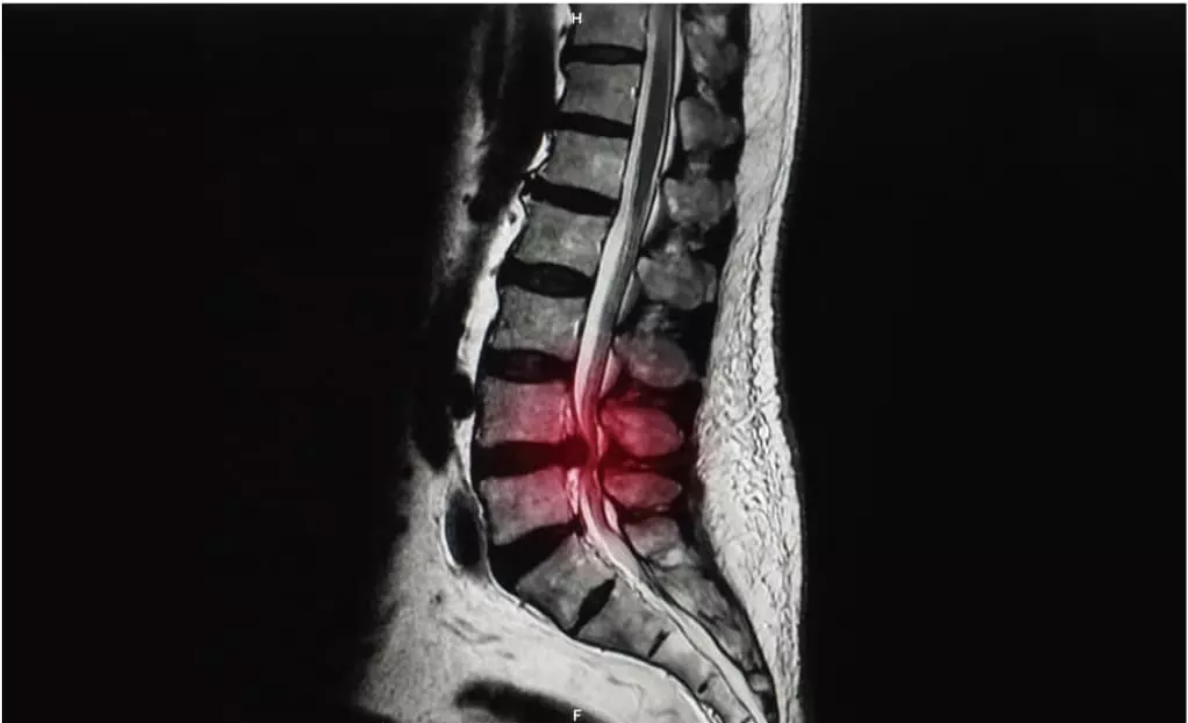

Before

After

脊柱管狭窄症とは?

体を支える脊柱(背骨)は、一つ一つのブロックである椎骨が約32個から34個連結してできています。

その椎骨には穴が存在し、背骨として形成されたときには脊柱管という脊髄・血管が走る道が作られます。

その脊柱管が加齢などの原因でズレが生じ、椎骨と椎骨の間の間隔が狭まったときに発症するのが脊柱管狭窄症です。

椎骨と椎骨の間隔が狭くなると、内部を走っている脊髄や血管が上下から圧迫されます。

それにより、痛みやしびれ(坐骨神経痛)といった症状が現れます。